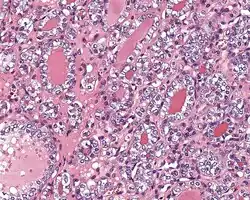

3) Predominantly follicular pattern of growth. Papillary structures should not be present. Further, solid, insular, or trabecular architecture must be <30% of the overall tumor for this category to still apply. Colloid (the material that thyroid follicular cells create) is easily identified throughout.

4) Must have the characteristic nuclear features of papillary thyroid carcinoma, although sometimes the features are patchy in distribution without all of the tumor showing those features. The nuclear features can be divided into three main categories:

- Nuclear size and shape: nuclear enlargement, nuclear elongation, and nuclear overlapping and crowding. Loss of nuclear polarity, with nuclei at the lumen, middle, or basal zone of the cells is also a helpful finding.

- Nuclear membrane irregularities: irregular nuclear contours, nuclear grooves and folds, "rat-bites" or demi-lune formations, and the presence of intranuclear cytoplasmic inclusions.

- Nuclear chromatin characteristics: nuclear chromatin clearing, often with condensation or margination along the nuclear membranes, resulting in accentuated nuclear margins, glassy nuclei, or fine, even delicate, powdery nuclear chromatin.